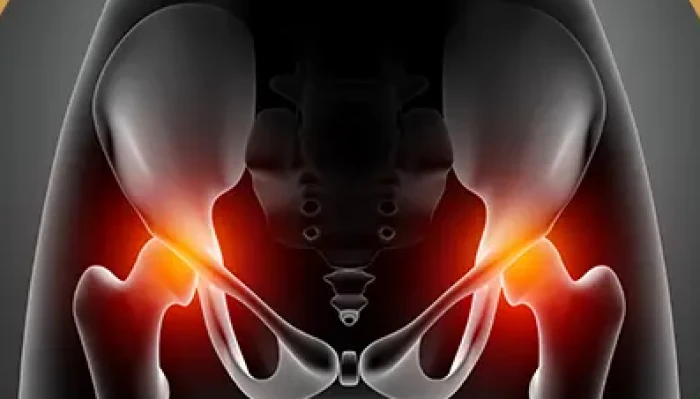

Condição degenerativa que causa dor e limitação de movimento na articulação do quadril.

Inflamação na lateral do quadril que causa dor localizada, tratável com fisioterapia.